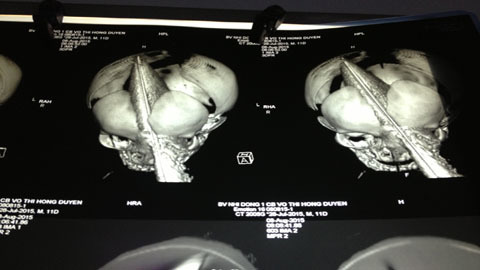

| Độ thương tổn do dao đâm xuyên sọ được đánh giá trên phim chụp. |